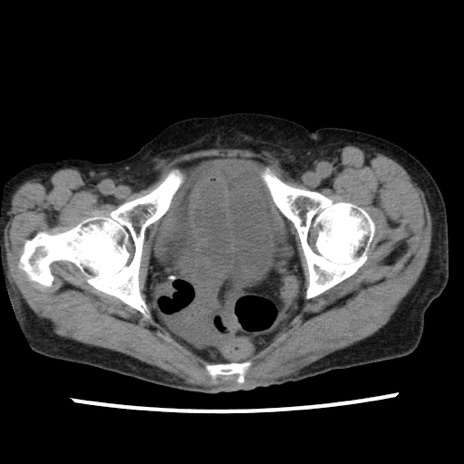

症例1(横断像)

【症例】80歳代女性

【主訴】腹痛

【現病歴】8時間前から腹痛あり来院。

【既往歴】糖尿病、脂質異常症、子宮体癌にて子宮全摘術

【身体所見】意識清明・会話良好だが腹痛で苦悶様、全腹部にわたって反跳痛と圧痛あり

【データ】WBC 13600、CRP 0.14、LDH 224、CK 90